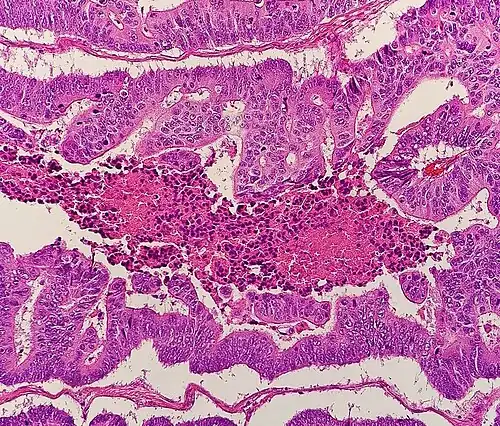

Histopathology

Relative incidence of various histopathological types of colorectal cancer. The vast majority of colorectal cancers are adenocarcinomas.[74]

Micrograph of colorectal adenocarcinoma, showing "dirty necrosis".

The histopathologic characteristics of the tumor are reported from the analysis of tissue taken from a biopsy or surgery. A pathology report contains a description of the microscopical characteristics of the tumor tissue, including both tumor cells and how the tumor invades into healthy tissues and finally if the tumor appears to be completely removed. The most common form of colon cancer is adenocarcinoma, constituting between 95%[75] to 98%[76] of all cases of colorectal cancer. Other, rarer types include lymphoma, adenosquamous and squamous cell carcinoma. Some subtypes have been found to be more aggressive.[77] Immunohistochemistry may be used in uncertain cases.